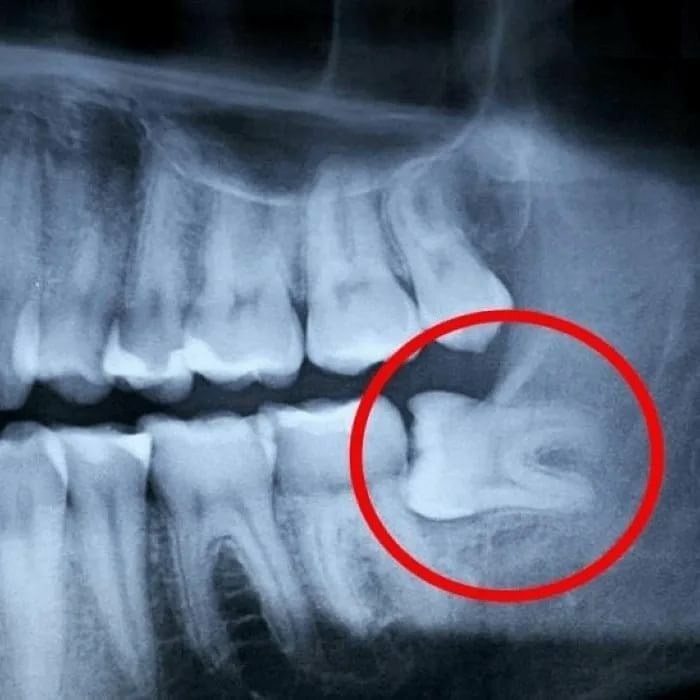

Снимок зубов для удаления зубов мудрости - это процедура, которая позволяет стоматологу увидеть, как расти зубы мудрости и определить, как лучше их удалить. Для этой процедуры используется рентгеновский аппарат, который делает снимок зубов.

Результаты снимка зубов для удаления зубов мудрости помогут стоматологу определить, как лучше всего удалить зубы мудрости. Снимок может также показать проблемы, связанные с ростом зубов мудрости, такие как инфекция или повреждение близлежащих зубов.